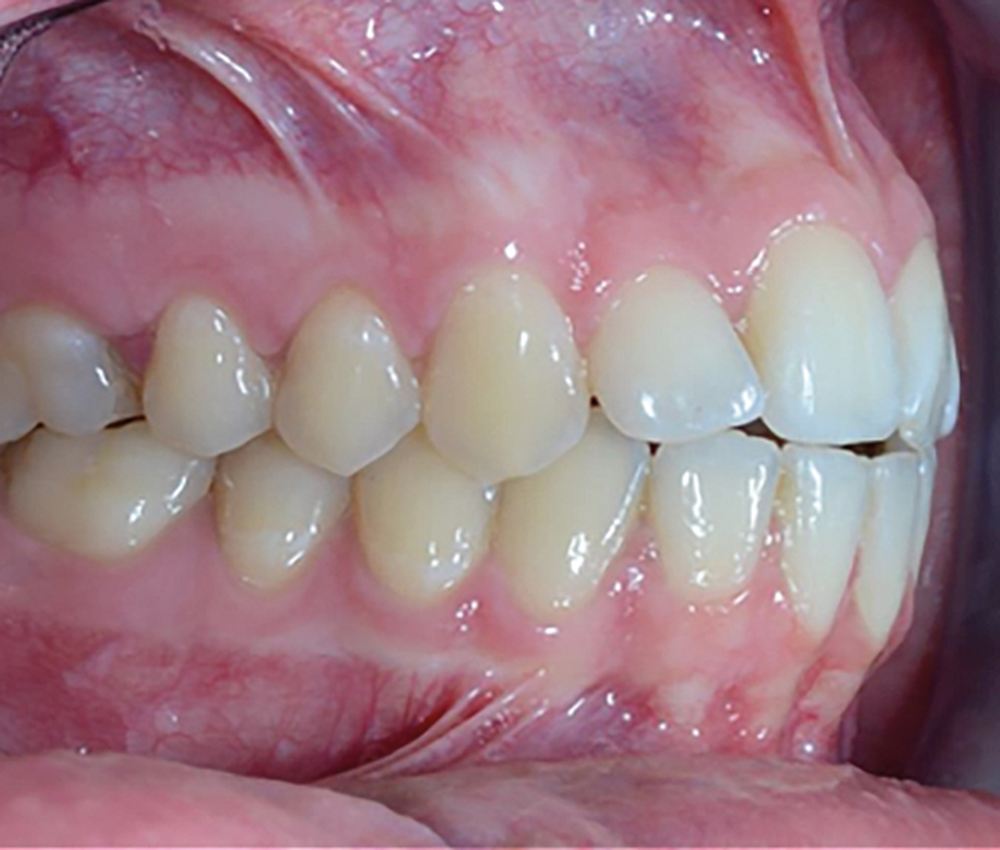

C’est à ces questions que nous permettront de répondre les deux premiers conférenciers, parodontologistes : le Dr Béatrice Straub nous présentera le renfort parodontal minéralisé, technique qu’elle a développée et pratique depuis de nombreuses années, pour éviter les préjudices des mouvements orthodontiques à risque, notamment lors des décompensations préchirurgicales (fig. 1a-d) ; le Pr Anton Sculean abordera le thème des greffes, avec leurs indications, les différentes techniques à privilégier et illustrera ses propos par de nombreux cas cliniques aux résultats esthétiques impressionnants.